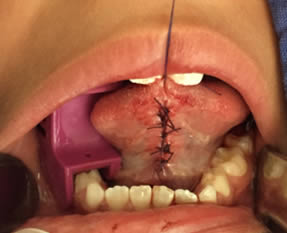

• Se irrigó bien la zona operatoria con solución fisiológica, se secó con gasa estéril, se revisó la hemostasia encontrándose en condiciones normales y se realizaron puntos simples de sutura utilizando Vicryl 3-0. Se terminó el acto quirúrgico sin accidentes ni incidentes. Figuras 11 y 12.

Figuras 11 y 12. Sutura y terminado del acto quirúrgico.